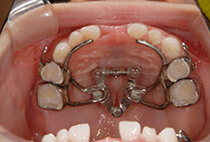

20代女性の患者さま。

八重歯の見た目が気になってご来院されましたが、実は顎の痛みや開口障害など、顎関節症の症状もありました。

そのため、かみ合わせと顎関節症の治療を同時に行ったにもかかわらず、2年間で治療が終了。

しっかり前歯を下げるために、インプラントアンカーを使用してコントロールしました。

かみ合わせが整うと咬筋の過緊張が改善。

過緊張による筋肉肥大も改善しフェイスラインもすっきりしました。